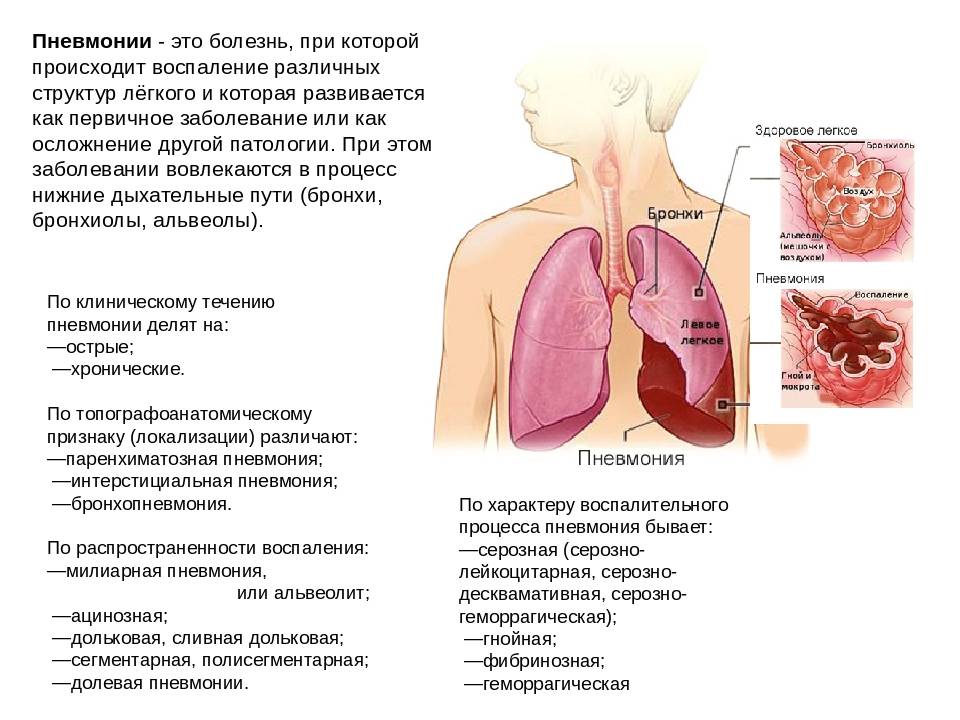

Острая внебольничная пневмония по МКБ-10: признаки и примеры